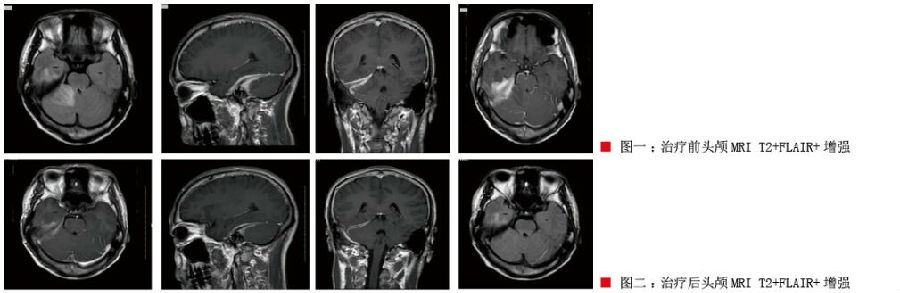

入院后行腰穿脑脊液常规示白细胞计数(WBC) 34×106/L,脑脊液蛋白 0.73g/L。头颅MRI示右侧岩部、右侧海绵窦区硬脑膜及右侧小脑幕异常增厚强化,考虑多发硬脑膜炎合并周围水肿、右侧大脑脚软脑膜炎可能性大,右侧乳突炎症(感染源可能?),鼻咽部右侧壁略增厚。考虑感染性病变可能(见图一)。

2、右侧乳突炎。给予头孢曲松钠抗感染、甘露醇减轻水肿、地塞米松消炎治疗2周。4月13日复查MRI+增强:右侧岩部、右侧海绵窦区硬脑膜及右侧小脑幕异常增厚强化,程度较前有所减轻,邻近右侧小脑半球水肿较前明显减轻、右侧颞枕叶水肿较前有减轻;右侧大脑脚软脑膜炎较前减轻(见图二)。出院后患者头痛缓解,肢体活动好。